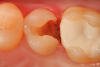

A 66 year-old female patientpresented with a "stained" occlusal groove in tooth No. 13 that did not "stick" with an explorer tip (Figure 1).  Upon radiographic examination (Figure 2), a rather large carious lesion was discovered that encroached upon the dental pulp.  There were no other clinical or subjective signs to alert the clinician or patient to the extent of the damage that had already occurred in the tooth. Figure 3 through Figure 5 show selective caries removal using a round end plastic polymer bur (SmartBurII, SS White).  Before caries removal, isolation of the operative quadrant was achieved using Isovac (Zyris). Because of its Knoop hardness of 90, SmartBurII allows for removal of infected dentin only, while allowing affected dentin to remain for potential remineralization with a bioactive liner or base material.

Fig 1.	A preoperative occlusal view of tooth No. 13 that has a “stain” in the occlusal groove that does not “stick” with an explorer.

Figure 1